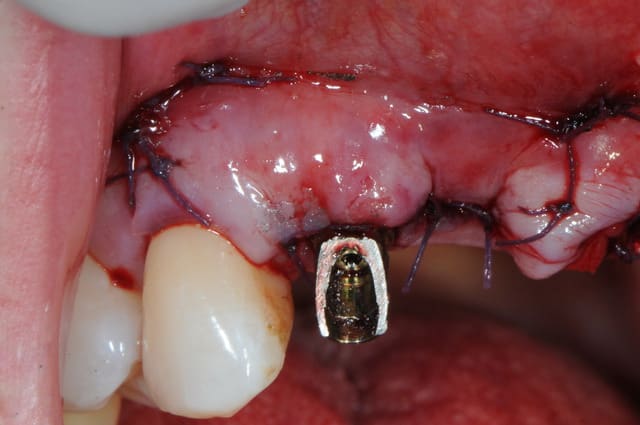

la ROG maintenant... ou "comment essayer de sauver les meubles"

Bonne idée d'implanter les latérales avant d'extraire les centrales pour conserver des repères dentaires.

Les implants auraient gagné à être un peu plus en position palatine ( je sais que tu sais...).

Puisque tu as voulu gérer en extraction implantation ce cas délicat avec une perte osseuse pourquoi avoir fait un lambeau ?

Une technique sans lambeau (avec comblement osseux des gap sur 12 et 22 et pourquoi pas des alvéoles de 11/21) me semblait plus appropriée pour réduire la perte osseuse et gingivale ainsi qu'une fermeture des sites de 11 et 21 à l'aide d' un greffon epithélio conjonctif circulaire.

A ta place j'attendrai que les implants soient ostéo intégrés avant de tenter quoique ce soit: ROG ou greffe conjonctif enfoui ...